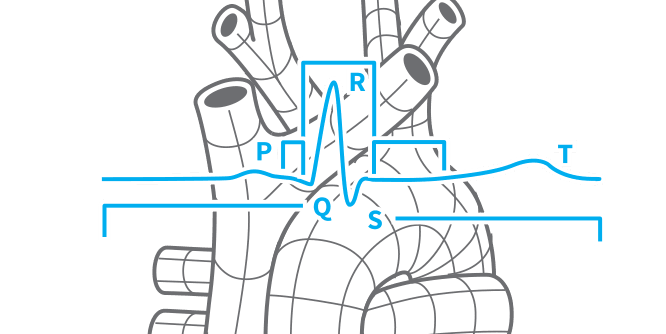

Designed for life science

LabChart is ideal for teaching the physiological principles that underlie many scientific and medical fields. Students get hands-on with real biological signals that demonstrate these core concepts in a dynamic and engaging way.